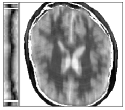

Figure 6 shows examples of the quantitative (magnitude) images of three of the 112 simulated inversion recovery measurements in the test dataset. We also show the regularization parameter-maps for regularization along the spatial directions and along the inversion-time direction generated by the network. The mean PSNR and SSIM of our proposed method is consistently higher for all considered acceleration factors, even compared to PDHG with regularization strength along spatial and inversion-time direction chosen by grid-search with access to the ground truth images (shown in Figure 8 and Table 2). The resulting parameter-maps after performing the regression on the reconstructed images are shown in Figure 7. Again, our proposed method results in the lowest RMS deviation from the ground truth images (Table 2).

CG-SENSE PDHG PDHG PDHG Target/ZF /

Example 1

Example 2

Example 3

CG-SENSE PDHG PDHG PDHG Ground Truth